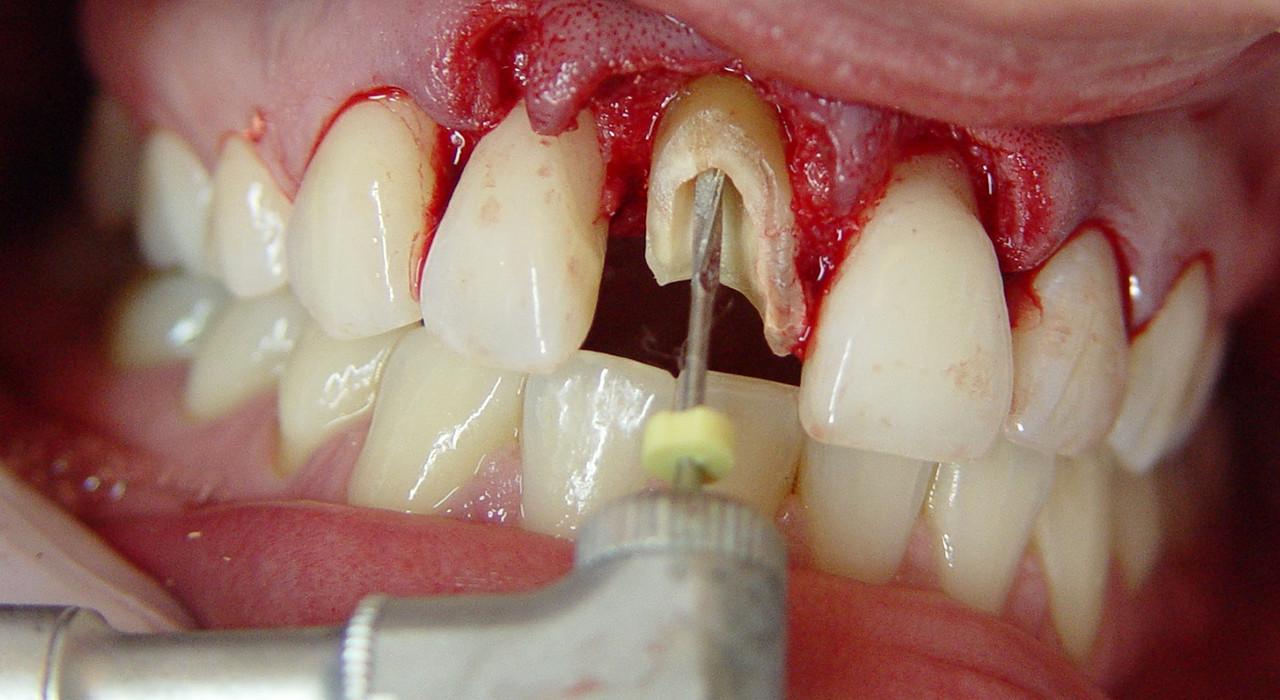

Insert cirugía Apical Endosuccess Apical Surgery AS3DAS6DAS9DASLD

From www.royal-dent.com

Insert cirugía Apical Endosuccess Apical Surgery AS3DAS6DAS9DASLD Stop Apical Endodoncia Traumatic injury to the surrounding (periapical) soft tissue should be avoided at all times. To this end, instrument stops should be used and instruments should be. Root canal shaping in the age of minimally invasive endodontics (mie) technology. The extent of apical enlargement can impact the outcome of endodontic treatment. This retrospective study evaluated cases of unintentional overfillings during root. Stop Apical Endodoncia.